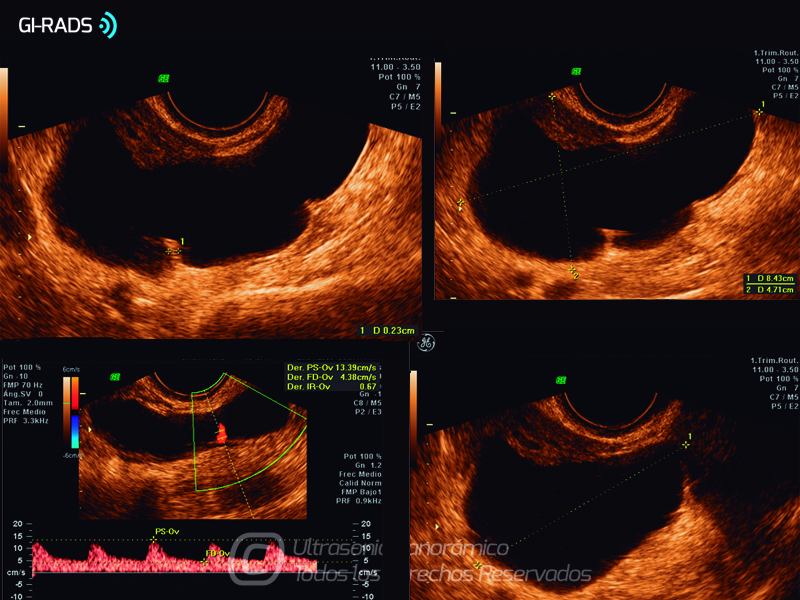

Patologías Benignas – Hidrosalpinx